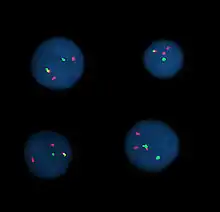

Fluorescent in situ hybridization

Fluorescent in situ hybridization (FISH) refers to using fluorescently labeled probe to hybridize to cytogenetic cell preparations.

Analysis

Analysis of FISH specimens is done by fluorescence microscopy by a clinical laboratory specialist in cytogenetics. For oncology generally a large number of interphase cells are scored in order to rule out low-level residual disease, generally between 200 and 1,000 cells are counted and scored. For congenital problems usually 20 metaphase cells are scored.